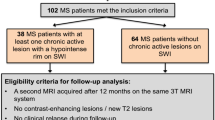

We retrospective identified MS patients scanned on the same 3 T MRI system presenting at least one supratentorial contrast-enhancing lesion (CEL) and a second MRI including susceptibility-weighted images after at least 3 months. On baseline MRI, pattern of contrast-enhancement was categorized as “nodular” or “ring-like”, apparent diffusion coefficient (ADC) maps were assessed for the presence of a peripheral hypointense rim. Lesion localization, quantitative volumes (ADC, lesion volume) and the presence of a central vein were assessed.

Eighty-nine acute contrast-enhancing lesions in 54 MS patients were included. On follow-up, 16/89 (18%) initially CELs converted into IRLs. CELs that converted into IRLs were larger and demonstrated significantly more often a ring-like contrast-enhancement pattern and a peripheral hypointense rim on ADC maps. Logistic regression model including the covariables pattern of contrast-enhancement and presence of a hypointense rim on ADC maps showed the best predictive performance (area under the curve = 0.932).

We retrospectively screened our database to identify patients fulfilling the following inclusion criteria: (1) diagnosis of definite MS according to the 2010 diagnostic criteria [9]; (2) at least 18 years of age; (3) a 3 T dataset acquired on the same MRI system including a 3D magnetization-prepared rapid acquisition gradient-echo (MPRAGE) sequence, a 3D fluid-attenuated inversion recovery (FLAIR)-data set, diffusion-weighted images including apparent diffusion coefficient (ADC) calculations and post-contrast T1-weighted images; (4) presence of at least one supratentorial CEL and (5) a second MRI (follow-up MRI) including SWI acquired on the same MRI system after at least 3 months. Trained neurologists assessed MS patients using the Expanded Disability Status Scale (EDSS) score on the days of the MRI examinations.